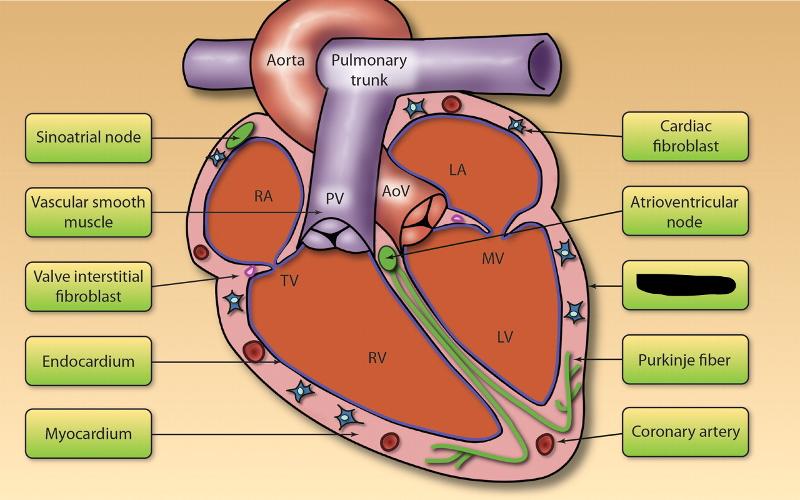

Anterior interventricular valve

Anterior interventricular sulcus

Posterior interventricular sulcus

Aortic Valve (=left semilunar)

Apex (of the heart)

Chordae tendineae

Circumflex branch (of the left coronary artery)

Coronary sinus

Endocardium

Epicardium

Intercalated disks

interventricular branch of the left coronary artery. = left anterior descending artery (LADA))

Left atrioventricular (=bicuspid, =mitral) valve

Left/right atrium

Left/right auricle

Left/right coronary artery

left/right ventricle

Myocardium

Papillary muscles

Pectinate muscles

Pulmonary trunk

Pulmonary valve (=right semilunar)

Right atrioventricular (=tricuspid) valve

Superior/inferior vena cava